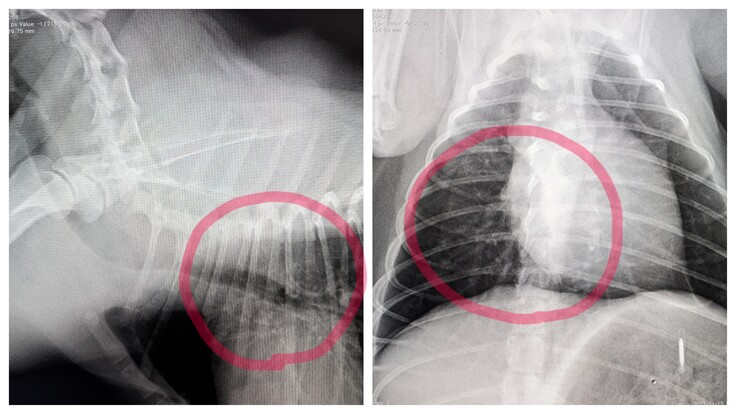

▲気管支炎。赤い◯の部分が本来ははっきりとしているのですが、白いモヤがかかっておりはっきりしません。